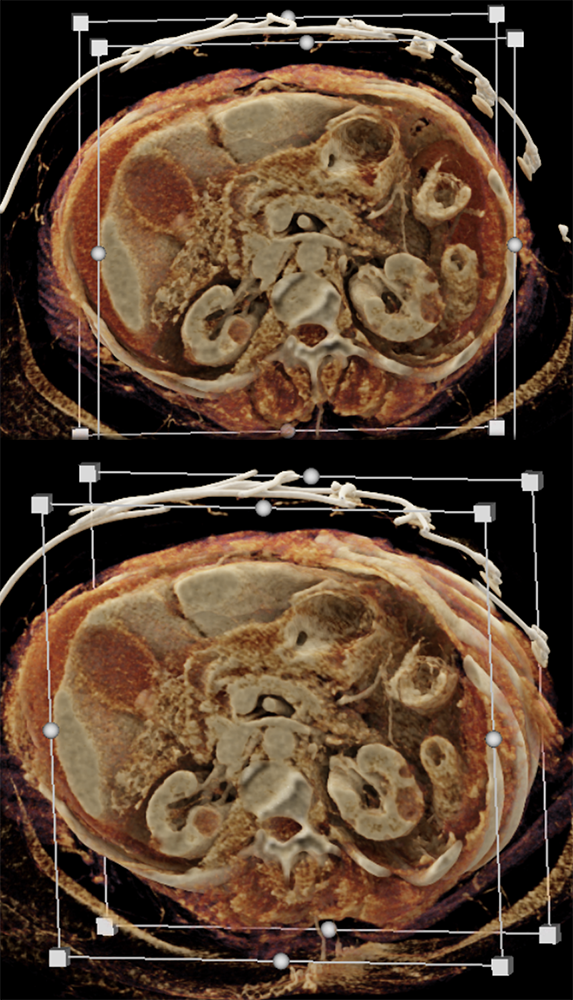

Abdominal Pain ![]() |

Gastric Ulcer with Perforation ![]() |

“Gastritis can be secondary to many etiologies including infection, systemic illness such as trauma or burns, and autoimmune disease. Peptic ulcer disease is most commonly caused by Helicobacter Pylori infection and chronic NSAID use . The most common sites for ulcer formation are the gastric antrum/pylorus and proximal duodenum. The resultant edema and fibrosis around the ulcer site can cause narrowing and eventual obstruction of the gastric outlet [9]. Prior to the widespread use of H2 blockers and proton pump inhibitors, peptic ulcer disease was the most common cause of gastric outlet obstruction, however in the era of H2 blockers, outlet obstruction now predicts malignancy. While endoscopy is the modality of choice for diagnosing gastritis, CT is often performed first particularly in the setting of acute abdominal pain.” Imaging of acute gastric emergencies: a case-based review Jetty S et al. Clinical Imaging 72 (2021) 97–113 |

“On imaging, it can be difficult to distinguish benign peptic ulcer disease from malignant causes of gastric outlet obstruction and biopsy is required for confirmation. Peptic ulcers can perforate and should be recognized on imaging.” Imaging of acute gastric emergencies: a case-based review Jetty S et al. Clinical Imaging 72 (2021) 97–113 |

“On CT, gastritis will appear as wall thickening with alternating hyper- and hypoattenuation representing mucosal enhancement and submucosal edema. The presence of mucosal enhancement (hyperemia) on CT suggests gastritis as the cause of gastric wall thickening. An uncommon form of gastritis is emphysematous gastritis. It is usually caused by gas-forming Escherichia coli. Initially obtained AXR may show mottled gas outlining the gastric wall. CT can confirm the diagnosis. Mottled gas can also be a sign of gastric pneumatosis from ischemia.” Imaging of acute gastric emergencies: a case-based review Jetty S et al. Clinical Imaging 72 (2021) 97–113 |